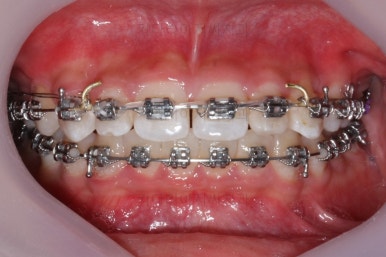

부산교정치과 키다리아저씨치과에서 치료한 이번 치료의 전후사진을 비교해 볼게요.

왼쪽이 치료 전, 오른쪽이 치료 후 모습입니다.

매우 복잡한 문제들을 복합적으로 가지고 있었던 경우였지만 만족할만한 결과를 얻을 수 있었어요.

치아는 매우 가지런해졌고 뾰족하던 앞니의 형태도 좋아졌어요.

매복되어 있던 송곳니도 잘 나왔고 과개교합도 물론 개선이 되었습니다.

얼굴모습은 크게 바뀌진 않았어요.

대신 웃거나 말하는 모습에서 드러나는 치열은 매우 예뻐졌어요.